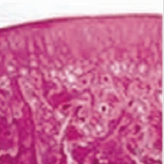

연골 퇴행 연골 퇴행

무엇보다 척추·관절 건강이 뒷받침 되어야 합니다. 자생 퇴행성 척추·관절 치료 한약은 진액을 보충하여 관절을 부드럽게 하고

연골을 보호 및 재생하여 퇴행성 질환을 효과적으로 치료합니다.